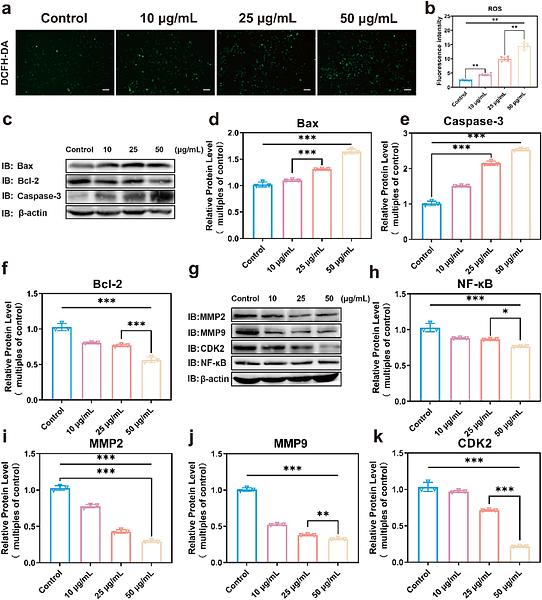

Mannose-Modified Multifunctional Iron-Based Nanozyme for Hepatocellular Carcinoma Treatment by Remodeling the Tumor Microenvironment

Author: Qi Liu, Ziwei Liang, Jiapu Wang, Yuhui Wang, Jie Wang, Shaojie Wang, Zhi Du, Liqin Zhao, Yan Wei, Di Huang

PMID: 39923382

期刊: Colloids And Surfaces B: Biointerfaces

应用: IF,WB

反应种属: Human

发表时间: 2025 Feb